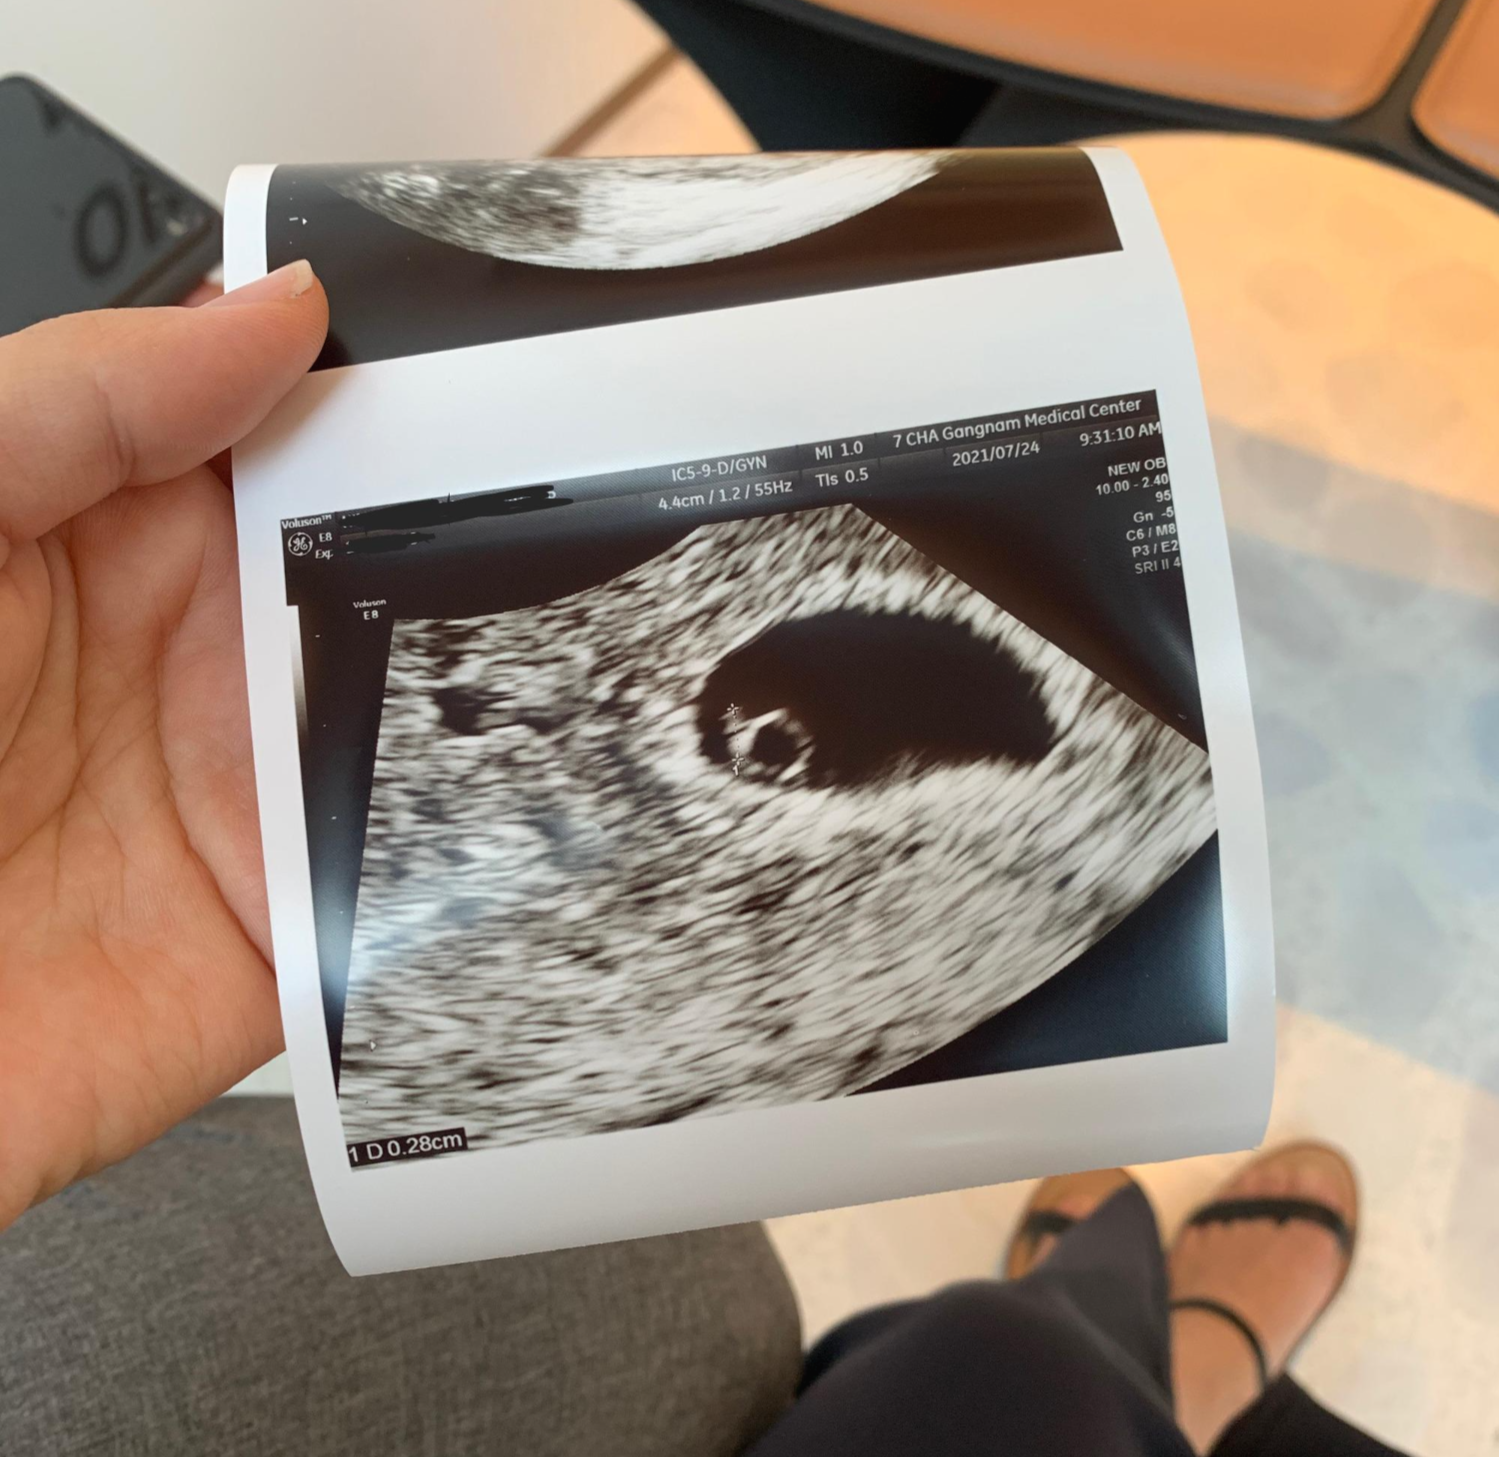

5주 4일 난황 및 심장소리 확인, 산전검사 진행

그 뒤 예정대로 병원간게 5주 4일인데요.

이미 난황과 아기, 심장이 생겨있었어요!

강남차병원은 병원가면 우선 초음파실에서 초음파 쌤한테 초음파 보고 교수님 진료를 하는데요.

초음파 쌤이 아무말 없이 심장소리를 틀어줘서 정말 깜짝 놀랐어요.

??????????????????????이거 심장소리예요????????

라고 물어봤던 기억이 아직도 생생해요 ㅎㅎ

사진에 커서있는 부분이 이미 아기가 생긴거고, 반짝반짝 심장도 뛰고 있는게 보이더라구요.

요때 아기는 0.28mm로 아주 작고 작았어요.

근데 심장이 반짝거리고 심장이 쿠슈쿠슈쿠슈 뛰고있는걸 보니 너무 신기하더라구요.

다만, 주수가 좀 일러서 심장 뛰는 속도는 조금 느리더라구요.

태아 심장박동수는 성인의 약 2배정도 되기 때문에 주수에 따라 다르겠지만 보통 120~160bpm정도 되는데요,

저때 꼬미 심박수는 5주 심박수 평균인 80~103bpm 사이인 102bpm정도 였던 걸로 기억해요 :)

아 사진에 아기집 왼쪽 위쪽으로 좀 까만 부분 보이시나요?

이 부분인데요.

피고임이라고 하더라구요.

착상하며 피고임이 발생할 수는 있는데 피고임이 커지면 아기집을 위협하기 때문에 위험해요.

저는 피고임이 크지는 않았는데 더 커지지 않도록 관리해주라고 하더라구요.